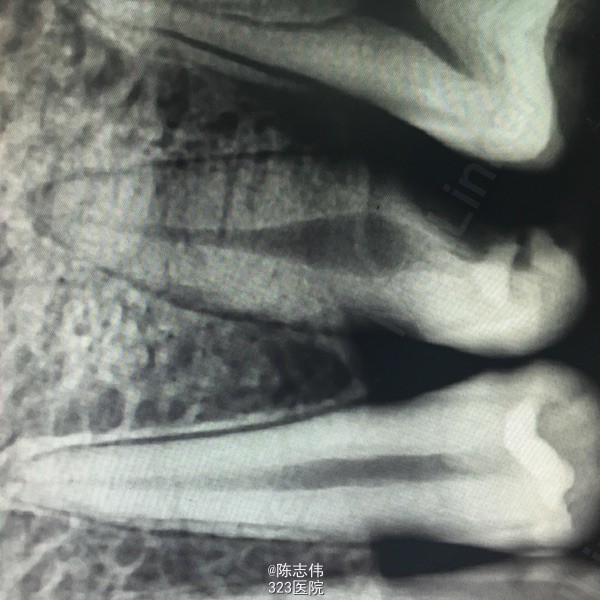

16近中颊部龋损,探深及龈下1mm,颌面白色充填物,冷(+) 松动(-) 叩(-)

x线示:16龋损近髓

17,45缺损及髓,根尖无明显异常